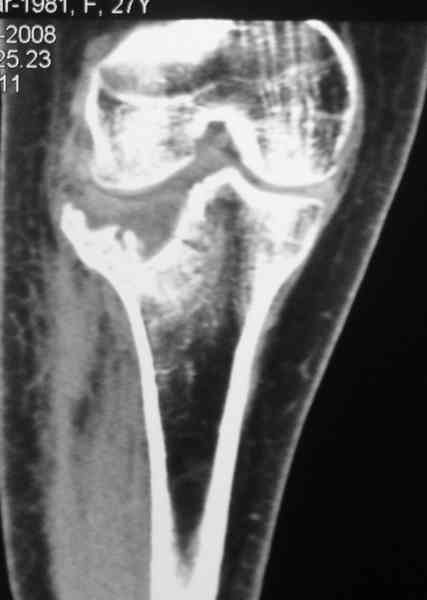

Есть ли возможность сделать КТ?

К большому сожалению КТ пока на ремонте, как запустять, сразу сделаю. Спасибо.

Я согласен с мнением доктора Соломина, что необходимо выполнить СТ. Это поможет Вам не только определить степень повреждения твёрдых тканей, но и увадеть степень сращения. Без СТ не возможно планировать дальнейшую тактику лечения.

У пациента основной проблемой является импрессионый перелом наружного мыщелка, уже неправильно сросшийся, по-видимому. Аппаратом закрыто можно только подправить угол на уровне метадиафиза. Что

улучшит разве что внешний вид конечности, но не решит основной проблемы - грубой деформации суставной поверхности.

Через 3 месяца после перелома все еще можно выделить отломки, очистить от костной мозоли и и восстановить анатомию суставной поверхности. Фиксировать компрессионными шурупами. Важно помнить, что наружный мыщелок должен быть на 4-5 мм выше внутреннего. Передняя крестообразная связка обычно остается с частью кости и важно фиксировать ее проволокой по Ли. После восстановления суставной поверхности весь комплекс суставной поверхности нужно фиксировать к диафизу, можно использовать пластинку с фиксированными шурупами с наружной поверхности или две обычные с двух сторон или аппарат Илизарова. Важно сохранить задний наклон плато приблизительно 7 градусов. При закрытии доступа бугристость б.б кости фиксировать двумя шурупами. Важно добиться стабильности для максимально ранней разработки. Операция сложная, но интересная.